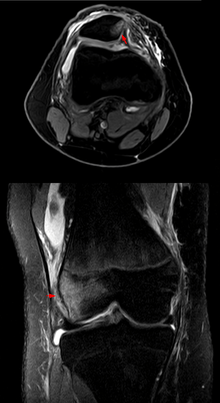

| Patella luxation on radiograph. Left before, right after reduction. After reduction the patella is still displaced. | |